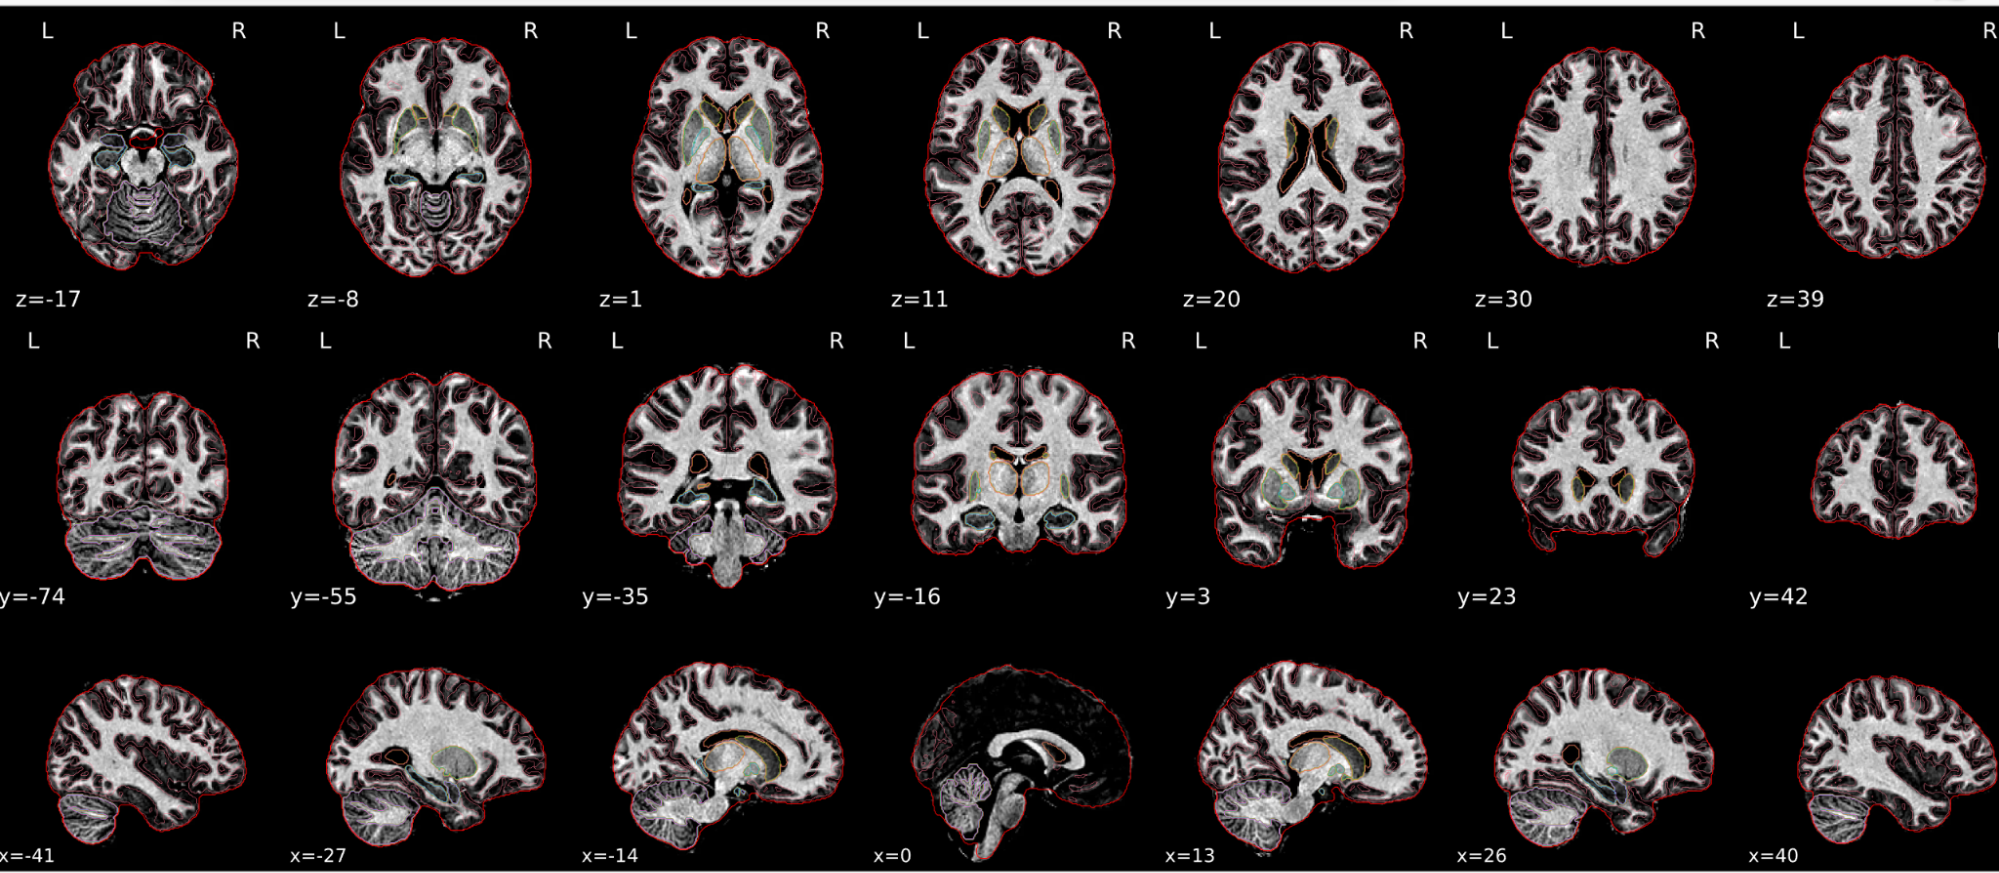

dT1w spatial normalisation

This QC step shows the registration of the T1 image to MNI space.

The registered T1 image is shown in the background with a brain atlas in MNI space as an overlay.

Example of a good subject

- If the registration performed well, you should see an overlap (i.e., correspondence of structures) between the MNI template and the T1 registered to the MNI space.

Example of a bad subject

- In case of poor registration, you should see a misalignment between the MNI template and the T1 (e.g., brain shifted down).

Summary

| good | bad |

|---|---|

| Structures of the MNI template and the registered T1 are well aligned | Structures of the MNI template and the registered T1 aren’t well aligned, e.g. brain is shifted downwards |